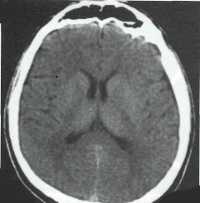

Хроническая субдуральная гематома

В конечном счете субдуральная гематома становится гиподенсной и может достигать ~ 0 HU, она может быть изоденсивной относительно ЦСЖ и может симулировать субдуральную гигрому.